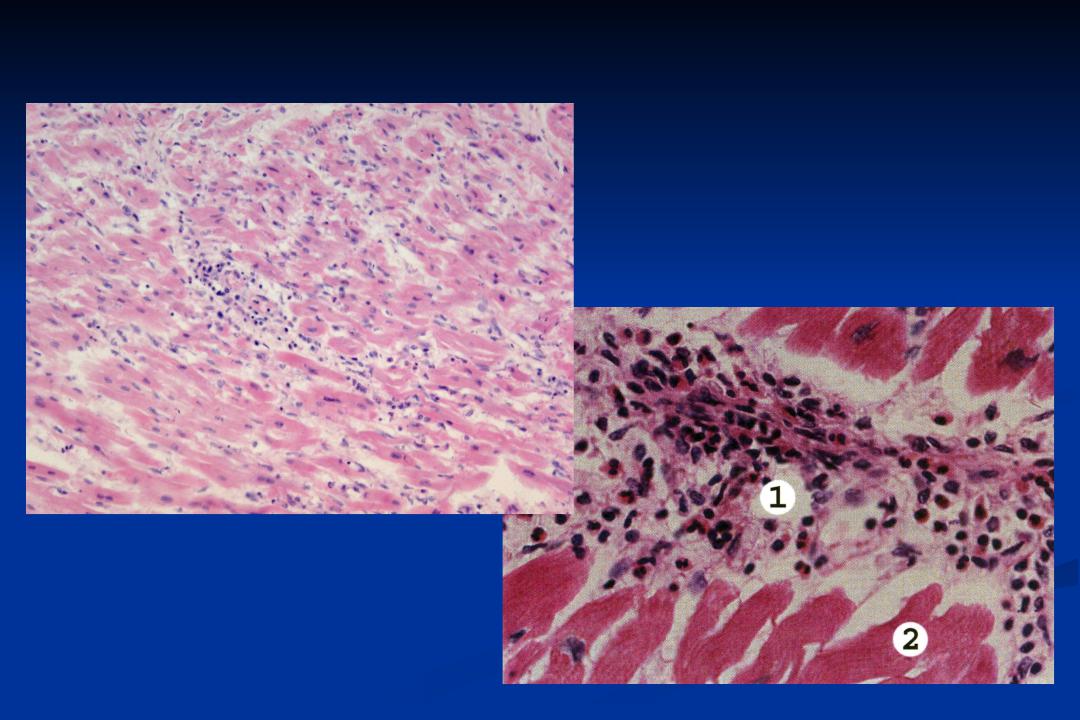

Межуточный миокардит: гистологические исследования

Раздел: Идеи и советы